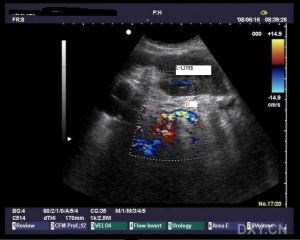

2.B型超聲檢查由於內鏡逆行膽道造影和經肝膽道造影是侵襲性檢查手段,B型超聲技術已成為對進行診斷的一種非侵襲性替代方法。雖然超聲本身不能確診C,也不能排除,但對篩選可疑患者確定進一步的損傷性檢查,以及鑑別診斷上可能有較大幫助。典型的B超聲像學為:①膽管管腔明顯狹窄,多呈均勻一致,一般為4mm,在節段性或局限性可見擴張膽管;②膽管壁明顯增厚,一般為4~5mm;③肝內膽管回聲增強;④累及膽囊可見壁增厚,功能減弱;⑤聲像圖無結石及腫瘤。學會識別在超音波中的表現是非常重要的,對以上聲像圖的準確判斷取決於超音波醫師臨床實踐的經驗。